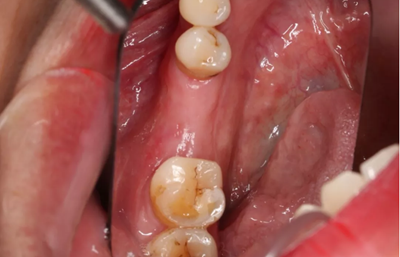

2、術(shù)前口腔內(nèi)照片

46牙烤瓷冠修復(fù),牙周紅腫,叩痛,松2度。骨吸收波及鄰牙,鄰牙牙周情況不佳,45牙松2度,47牙松1度。

(攝于2016年8月31日,反光板協(xié)助拍攝)